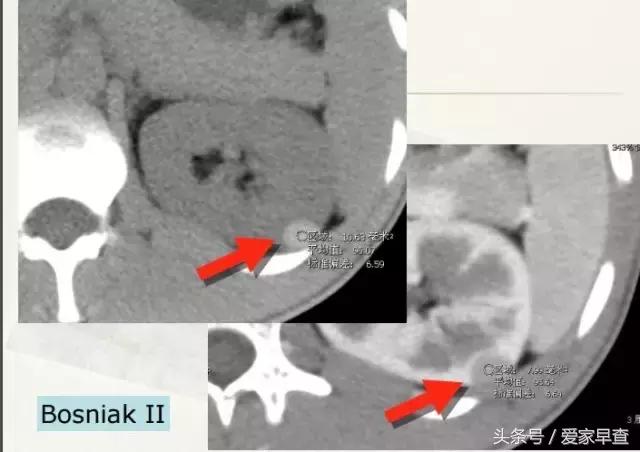

我们现在临床上采取的一个方法就是把各种各样的不同类型的囊肿,把它归成不同的分型。这个分型比较公认的一个分型叫Bosniak。 这个分型为什么被接受呢?是因为它跟临床的契合度非常好。比方说,如果我诊断是BosniakⅠ型,那就认为这是一个单纯囊肿,而单纯囊肿的恶性可能性几乎是零。如果是一个诊断为了BosniakⅣ型,可以认为它是囊性肾癌,看起来很好,但有一个前提,你要去做这个分型,必须要做增强扫描。

这张片子上这两个囊肿虽然也叫囊肿,但是它跟刚才那张片子上的那种不太一样的。你这个囊肿看到箭头所示是有一些分隔,还有一个稍微厚点儿的壁。但是它又不那么大,那我们就把它划成BosniakⅡ。BosniakⅡ的恶性可能性有多少呢?是小于0.5%,几乎是不太可能是恶性的,如果它最终变成恶性,就跟中彩票差不多。这种当它也不太大的时候,也是不需要处理的。